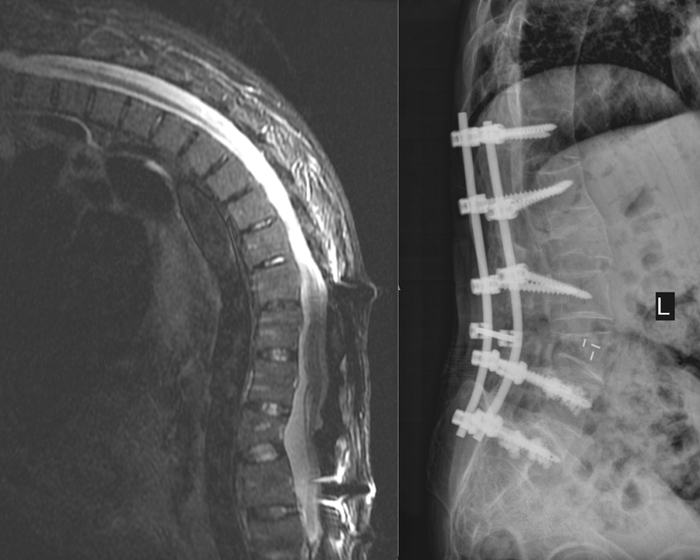

术前检查(左)和术后检查结果(右)

家礼医院骨科主任尹绍猛亲自为谢孟元接诊后,发现他的病情较为特殊:「患者是强直性脊柱炎晚期,出现了非常严重的后凸畸形,从片子上看达到了 90 度左右,由于患者已经做过一次手术,把整个腰背部的紧绷系结构都给破坏掉了,再次手术无疑会增加很大难度。」

「传统的经椎弓根截骨矫正的度数在 15 度左右,但这位病人用传统的治疗方式效果不好,所以运用腰椎椎体的结构矫形手术,实现了 30 度的矫形。」尹绍猛说。